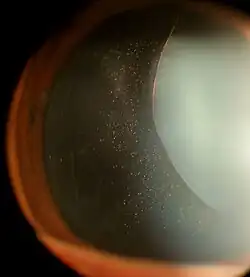

| Ectopia lentis in Marfan syndrome: Zonular fibers are seen. | |

In Marfan syndrome, the health of the eye can be affected in many ways, but the principal change is partial lens dislocation, where the lens is shifted out of its normal position.[18] This occurs because of weakness in the ciliary zonules, the connective tissue strands which suspend the lens within the eye. The mutations responsible for Marfan syndrome weaken the zonules and cause them to stretch. The inferior zonules are most frequently stretched resulting in the lens shifting upwards and outwards, but it can shift in other directions as well. Nearsightedness (myopia), and blurred vision are common due to connective tissue defects in the eye.[19] Farsightedness can also result particularly if the lens is highly subluxated. Subluxation (partial dislocation) of the lens can be detected clinically in about 60% of people with Marfan syndrome by the use of a slit-lamp biomicroscope.[19] If the lens subluxation is subtle, then imaging with high-resolution ultrasound biomicroscopy might be used.[20]